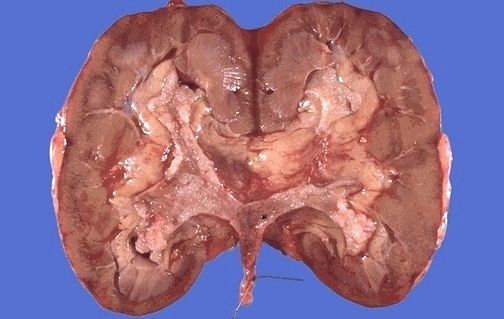

| Tumor de Wilms |

Image:

Renal059 (image/jpeg)